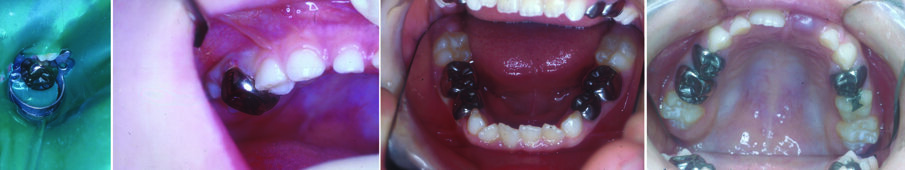

Figure 10 (a&b). A patient treated by the author received 7 SSCs using the hall technique. No LA, rubber dam, caries removal or drills were used. They remained free from clinical and radiographic signs and symptoms of pain or sepsis. Compare these with figures 3 (c & d) . Tooth 74 was extracted as it was not restorable.

Multiple SSCs using the Hall technique could be placed in one patient over several appointments without any local anaesthesia or drilling (see Figure 10). It is possible to place two SSC using the Hall technique in one appointment. This is possible in: a) contra-lateral primary molars in the same arch, for example placement of two SSC on upper Es (teeth 55 and 65) or lower Ds (74, 84). b) Diagonal teeth in opposing arches, for example, placement of SSCs on tooth 55 and 75, or placement of SSCs on 65 and 85.